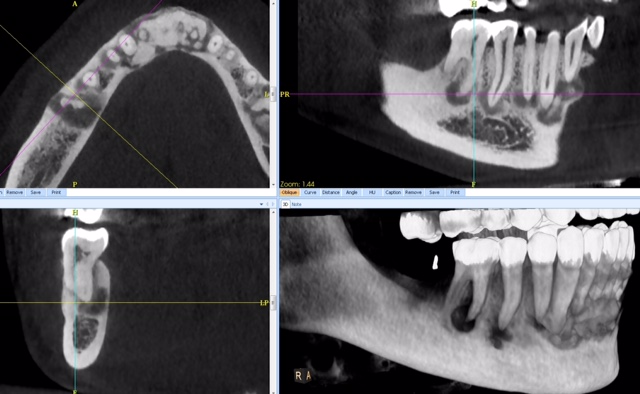

CBCT :

A. Observez sur les reconstructions axiale et panoramique les lésions apicales de :

a.46

b.43

c.et du bloc incisif.

B. Comment les décririez-vous ?

1. Lacunaire (hypodensité homogène) ?

2. En cocarde ou en cible à centre dense (lacune centrée par une zone centrale calcifiée) ?

3. Presque complètement dense, calcifiée (blanche), entourée d’un liseré clair (noir) ?